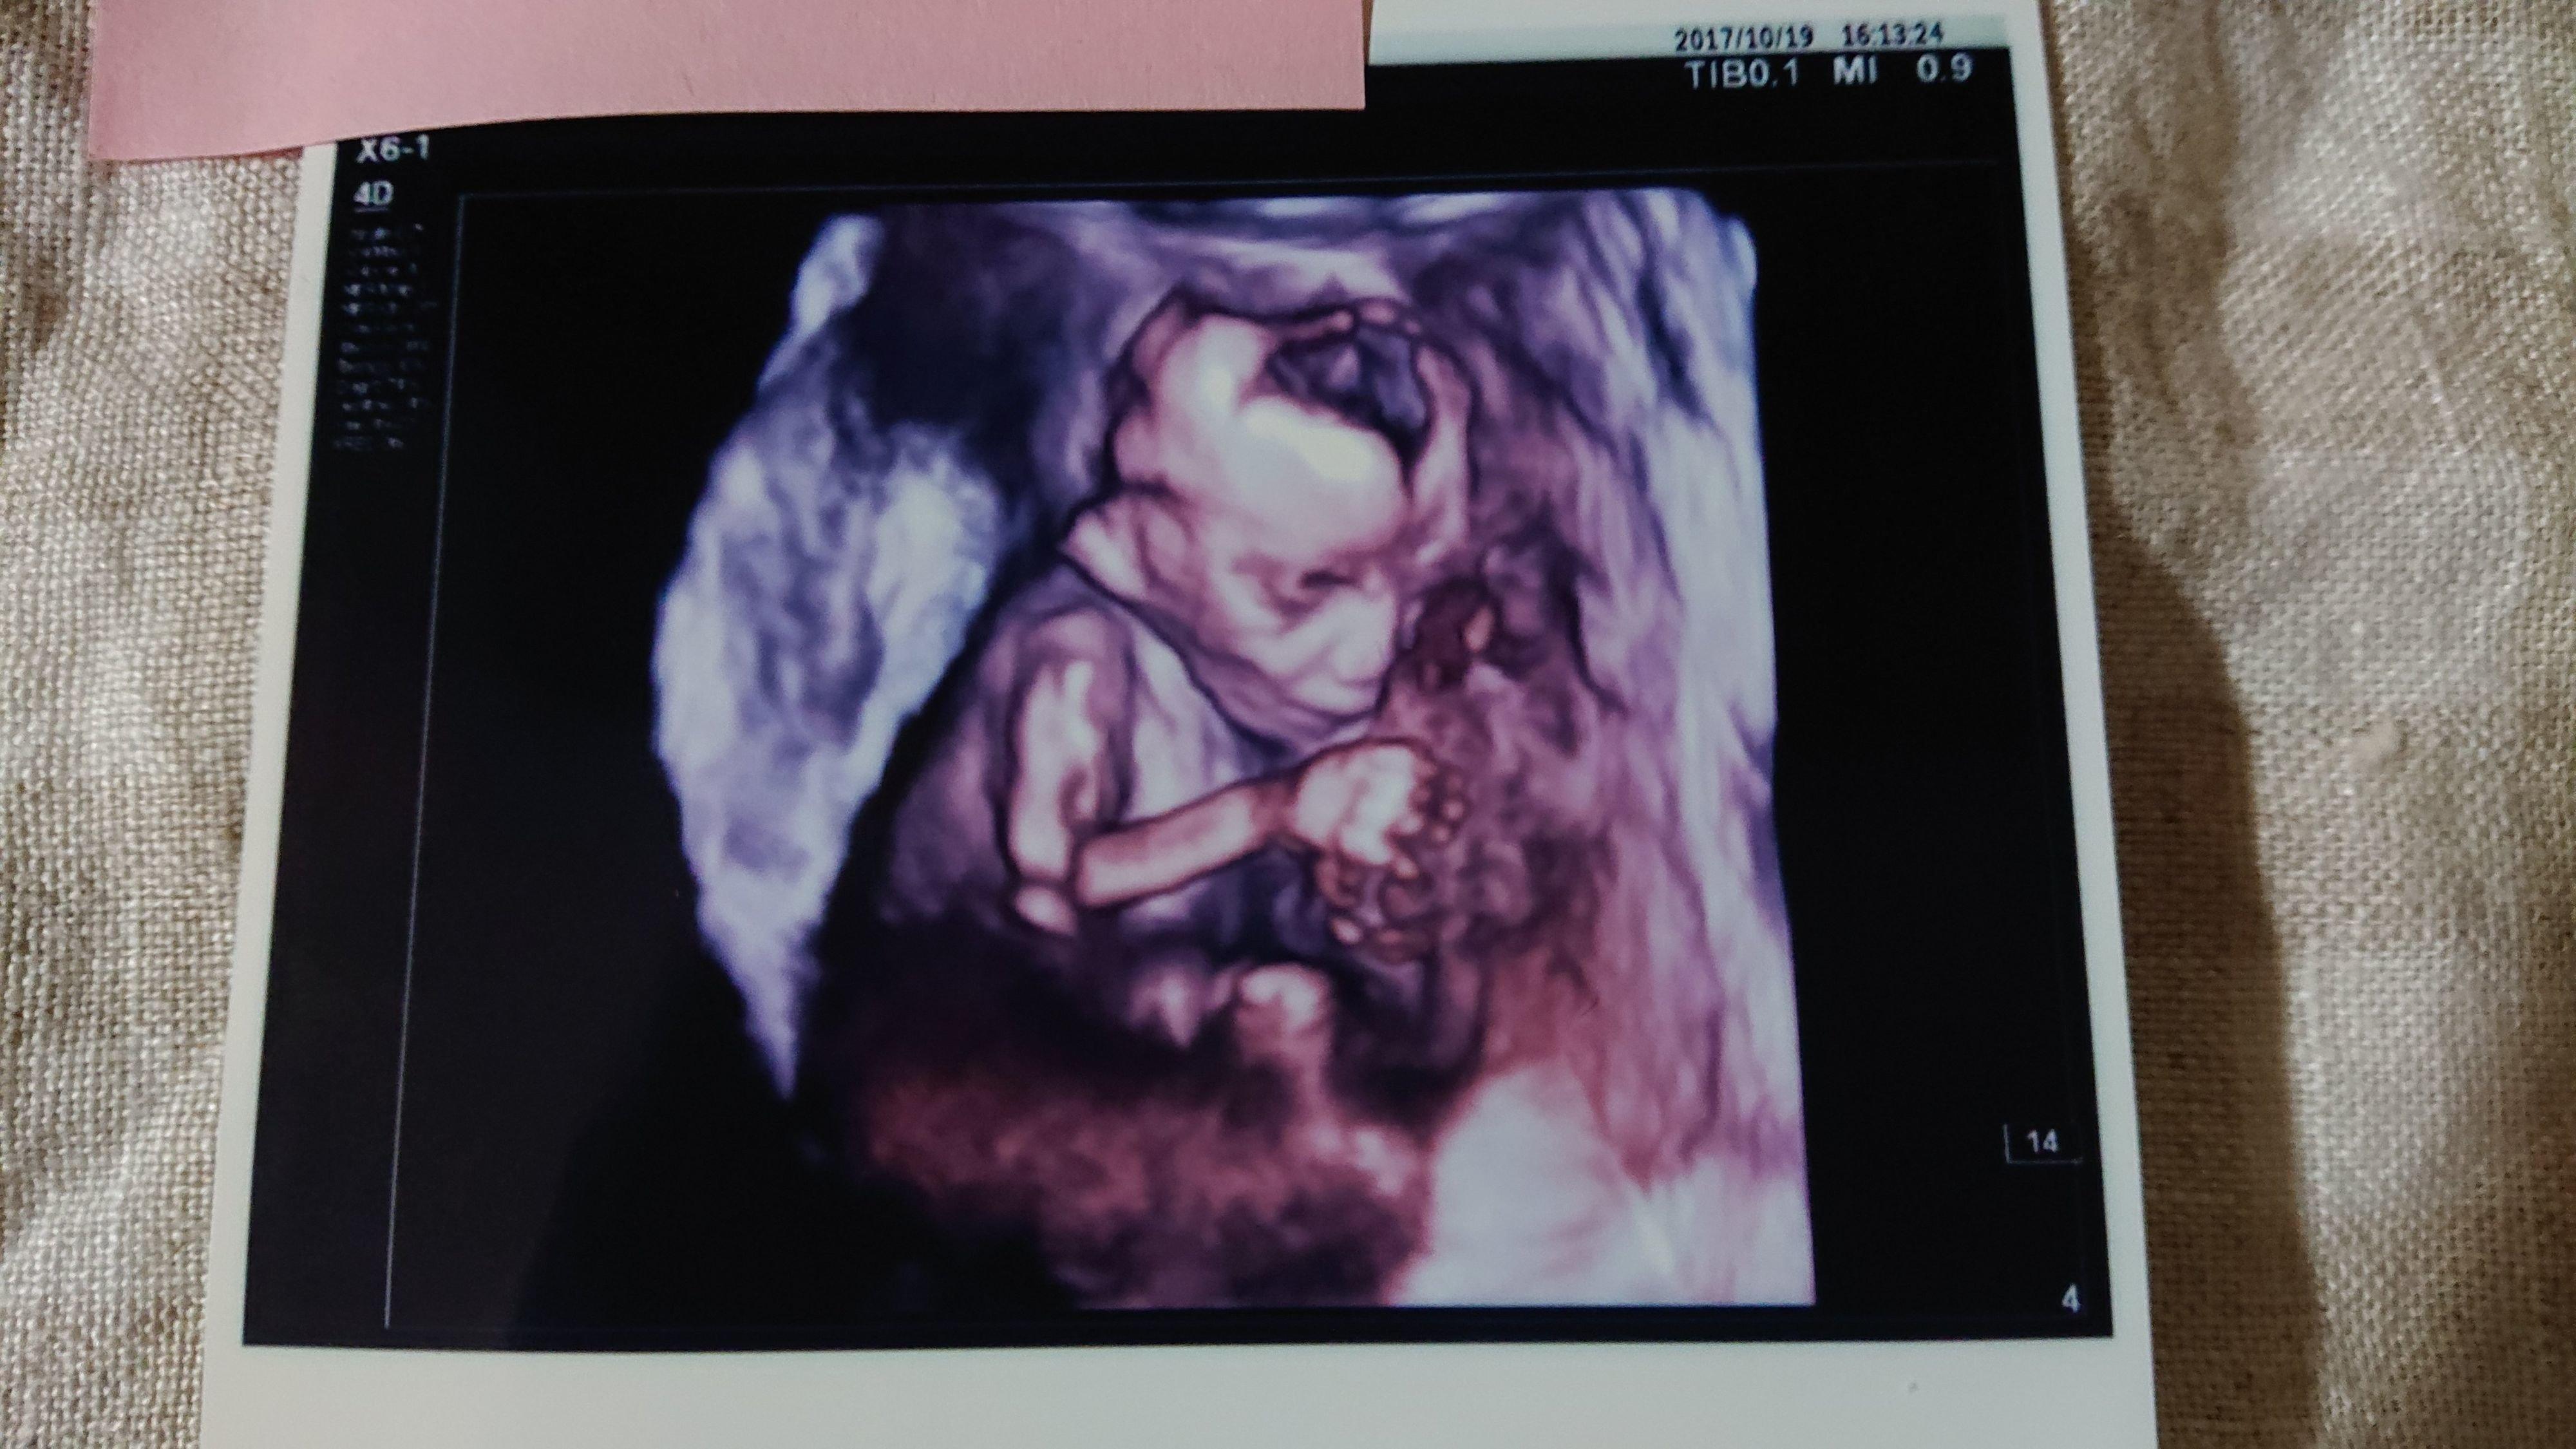

《妊娠30週目のエコー写真》

妊娠30週目、年内最後に受けた妊婦健診で頸管長が一気に短くなったことが判明。頸管長17mmとなり切迫早産の為、緊急入院しました。そして、なぜかこのタイミングで逆子になってしまいました。「赤ちゃんが、まわった感じしなかった?」と看護師に言われましたが、私にはサッパリ気が付きませんでした。その影響もあり、今まで全く頭になかった“帝王切開”の言葉を聞くことになりました。妊婦健診の後は、入院中のベッドの上で“帝王切開“を検索しまくりました。